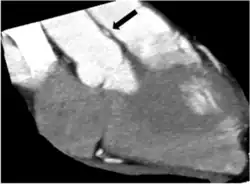

Anomalous origin of a coronary artery from the opposite sinus are relevant on a clinical level due to a significant association with sudden cardiac death, if they are accompanied by intramural course. Indeed, the main feature responsible for adverse outcomes is the “intramural” course (sometimes improperly referred to as inter-arterial) characterized by an acute ostial angulation (tangential course), “slit-like” ostium (compressed inside the aortic wall), and a proximal or initial section penetrating into the aortic tunica media (coronary arteries normally take off at a 90 degree angle) with subsequent course reaching the “correct” side of the heart. As a consequence, lateral compression of the coronary artery leads to coronary luminal (inside opening) narrowing, with reduced supply of blood and oxygen to the depending myocardial tissue, that is phasic (worse in systole, the phase of cardiac contraction, and tachycardia). Furthermore, the intramural segment of the ectopic artery, located inside the aorta, is typically but variably “hypoplastic”, smaller in circumference than the distal, extramural segments (it is unable to grow properly either before or after birth).

Various imaging tests have a potential to identify coronary artery anomalies. Echocardiography (ultrasound scanning of the heart) is simple, non-invasive and economical. Its use for CAAs screening is limited because its diagnostic sensitivity is highly dependent on the operator's skills and is significantly lower in larger individuals (>40 kg). The diagnostic power of echocardiography is generally poor in most cases after infancy. Especially if clinical suspicion for CAAs is high (e.g. syncope following exertion and/or history of aborted sudden cardiac death). Cardiac magnetic resonance (CMR) is an excellent tool to identify coronary artery anomalies with a significantly higher diagnostic accuracy than standard echocardiography. Compared to CMR, coronary computed tomographic angiography (CCTA) provides more precise assessment of coronary anatomy, course and degree of stenosis, but its clinical use for screening is strongly limited by its cost, the need for ionizing radiation, intravenous contrast and, in many cases, drugs administration. Assessment of severity of stenosis is best achieved by intravascular ultrasound (IVUS) imaging and it should be considered in known carriers of ACAOS-IM or that have symptoms or positive stress test results or are involved in competitive exercises. IVUS consists of cross-sectional imaging of coronary arteries in a catheterization laboratory by advancing a thin probe inside the vascular lumen, obtaining precise in-vivo information about degree of area stenosis in different arterial segments, providing a solid basis for treatment strategies.